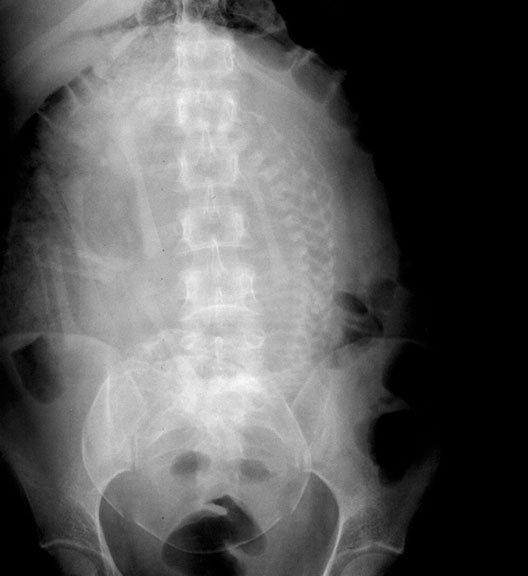

Pregnant Woman

Roll mouse over image to display labels.

1. Fetal spine

2. Fetal skull